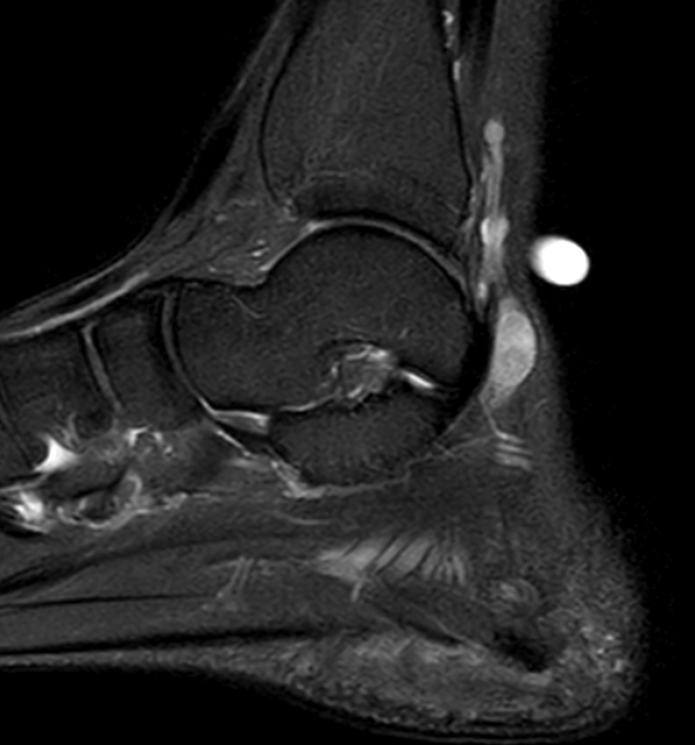

- heterogenous mass on MRI

GCT flexor tendon sheath

GCT of tibialis posterior tendon sheath